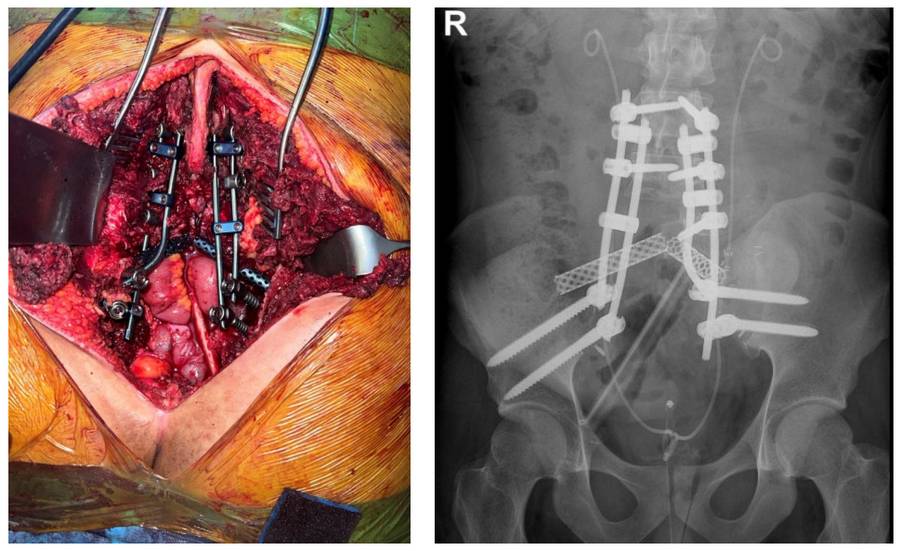

Neoadjuvan kemoterapiyi takiben iliak kanat posterior ve beşinci lomber vertebra yarısı dahil total sakrektomi sonrası titanyum kafes, vaskülerize fibula ve lumbopelvik fiksasyon ile rekonstrüksiyon işlemi uygulandı

Ameliyat Esnası ve Sonrası: Total sakrektomi sonrası fibula, titanyum kafesler ve lumbopelvik fiksasyon ile yapılan rekonstrüksiyon işleminin klinik ve röntgen görüntüsü